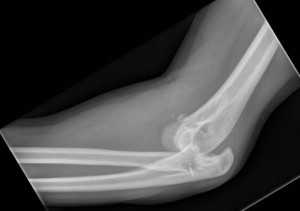

(Слева) На боковой рентгенограмме у четырехлетнего мальчика определяется надмыщелковый перелом плечевой кости после падения на выпрямленную руку. Обратите внимание на смещение головки кзади относительно линии вдоль переднего коркового слоя дистального эпиметафиза плечевой кости. Положительный симптом жировой подушки подтверждает внутрисуставную природу перелома. Следовательно, это действительно чрезмыщелковый перелом.

(Справа) На передне-задней рентгенограмме у этого же пациента не видна линия перелома, что является характерным для этой возрастной группы, кроме случаев с переломом с более значительным смещением.

(Слева) В боковой проекции у женщины 87 лет после падения определяется повреждение Гартланда II типа с задним смещением мыщелков плечевой кости относительно диафиза и задним угловым отклонением, но с сохранением контакта с задним кортикальным слоем.

(Справа) На снимке в боковой проекции у девятилетнего ребенка определяется полное смещение кзади мыщелков плечевой кости и отсутствие контакта между отломками, составляющими повреждение Гартланда III типа. Поскольку перелом не переходит на мыщелки, он является истинным надмыщелковым переломом.